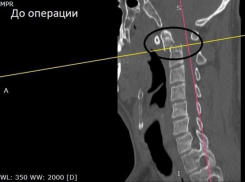

Общество Воронежец упал в подъезде дома и сломал себе шейный позвонок

31.07.2024

Мужчину пришлось оперировать